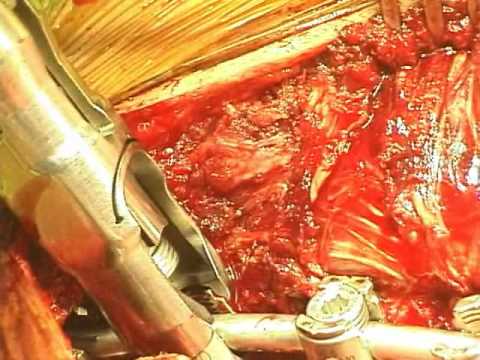

Korekcja skoliozy z wykonaniem spondylodezy tylnej

Na filmie obserwujemy operację korekcji skoliozy idiopatycznej wykonaną przez dr Petera Newton z Rady Children's Hospital w San Diego. Operacja polega na wprowadzeniu śrub transpedikularnych pod różnymi...

Osteotomia Ponte i spondylodeza tylna w leczeniu skoliozy

Na filmie widzimy operację skoliozy z zastosowaniem spondylodezy tylnej, wykonywaną przez dr Petera O. Newton w szpitalu Rady Children w San Diego. Dr Newton jest członkiem Grupy Badawczej Harms - grupy...

Torakoskopowe usunięcie dysku z dostępu przedniego i zastosowanie...

Na filmie widzimy operację młodzieńczej skoliozy idiopatycznej (AIS) - torakoskopowe usunięcie dysku z dostępu przedniego i zastosowanie spondylodezy tylnej. Operację wykonał dr Peter O. Newton w szpitalu...

Torakoskopowe usunięcie dysku z dostępu przedniego i zastosowanie...

Na filmie widzimy operację młodzieńczej skoliozy idiopatycznej (AIS) - torakoskopowe usunięcie dysku z dostępu przedniego i zastosowanie spondylodezy tylnej. Operację wykonał dr Peter O. Newton w szpitalu...

Torakoskopowa spondylodeza przednia w leczeniu skoliozy idiopatycznej

Na filmie widzimy operację skoliozy idiopatycznej, z zastosowaniem torakoskopowej spondylodezy przedniej , wykonywaną przez dr Petera O. Newton w szpitalu Rady Children w San Diego. Dr Newton jest członkiem...

Leczenie operacyjne idiopatycznej skoliozy - spondylodeza tylna

Na filmie widzimy operację skoliozy idiopatycznej z zastosowaniem spondylodezy tylnej, wykonywaną przez dr Petera O. Newton w szpitalu Rady Children w San Diego. Dr Newton jest członkiem Grupy Badawczej...